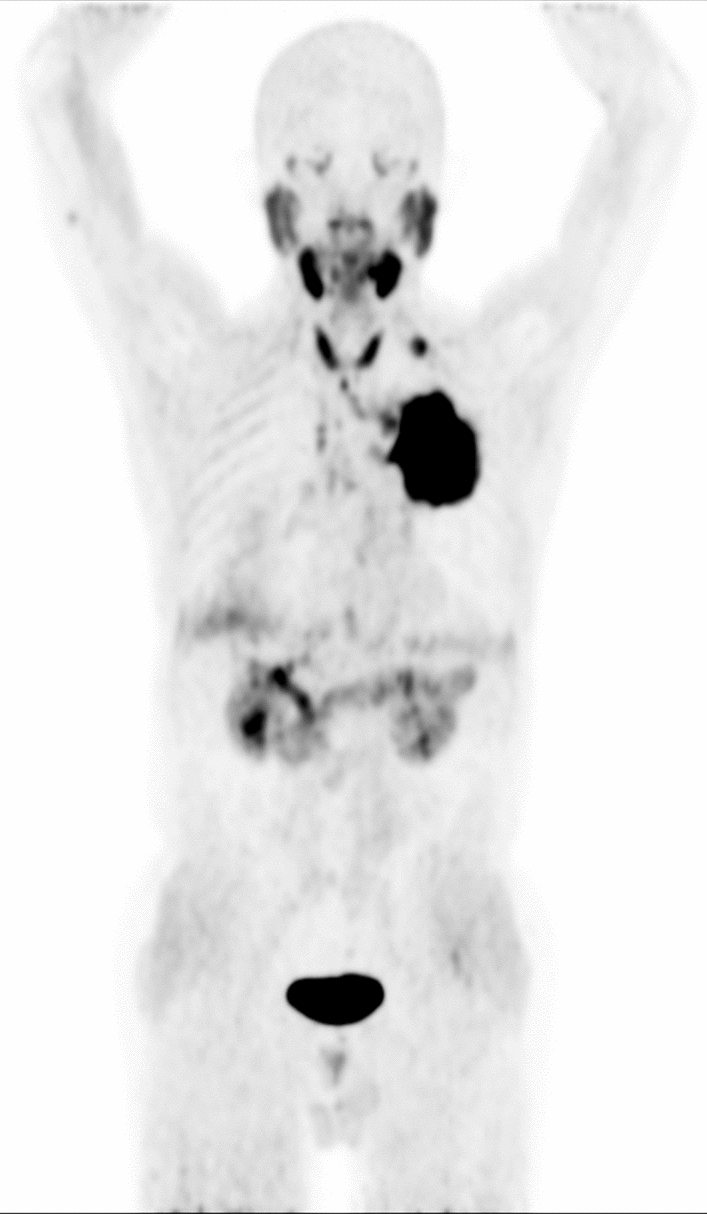

Background: Many patients undergoing [18F] AlF-NOTA-FAPI-04 (18F-FAPI) PET/CT demonstrated diffuse thyroid uptake. These findings created challenges for accurate interpretation due to the limited understanding of physiological and non-oncologic causes of diffuse 18F-FAPI uptake in the thyroid. This retrospective study examined patients who underwent 18F-FAPI PET/CT imaging with diffuse thyroid uptake. It quantitatively assessed normal thyroid uptake, compared 18F-FAPI uptake between normal and diseased thyroids, and explored potential associations with diffuse thyroid uptake. The study may improve the accuracy of 18F-FAPI PET/CT interpretation for thyroid and facilitate appropriate management of diffuse thyroid uptake on 18F-FAPI PET/CT.

Results: A total of 38 patients were included in this study based on the inclusion criteria. The mean SUVmax, SUVmean, and TBR of normal thyroid were 7.09 ± 3.83, 4.24 ± 2.25 and 3.93 ± 1.73, respectively. Quantitative analysis revealed no significant asymmetry in 18F-FAPI uptake between the right and left thyroid lobes (SUVmax: right 6.69 ± 2.96 vs. left 6.54 ± 3.28, p = 0.84; SUVmean: right 4.19 ± 1.73 vs. left 4.18 ± 1.97, p = 0.98), consistent with the diffuse uptake pattern observed. There was no significant correlation between Hashimoto thyroiditis, serum TSH levels, and the degree of diffuse thyroid uptake (all p > 0.05 for SUVmax, SUVmean, and TBR). Furthermore, no association was observed between sex, age, immunotherapy, and diffuse thyroid uptake (p > 0.05).

Conclusions: Diffuse uptake of 18F-FAPI in the thyroid may not significantly relate to Hashimoto thyroiditis or abnormal serum TSH levels. Lesions on 18F-FAPI PET/CT scans might be hard to detect due to the moderate uptake in normal thyroid tissue.